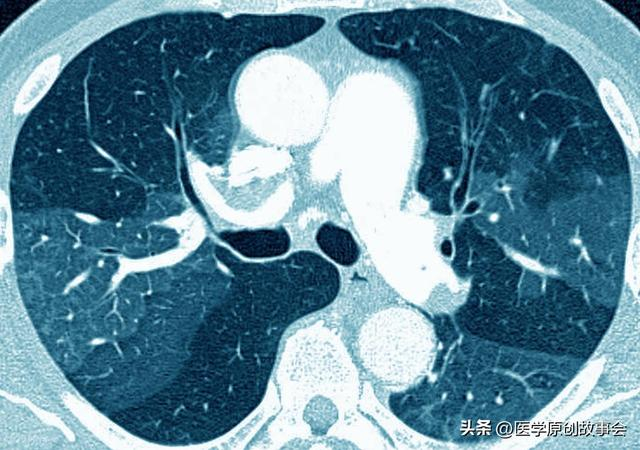

现在,重视体检的人越来越多了,很多人到医院检查胸部CT的时候发现肺部有结节,虽然很多肺结节都是良性的,但是也有一些肺结节,却属于恶性病变,问题来了,如何来判断肺结节到底是良性的,还是恶性的呢?

第三,看肺结节的密度

根据密度的不同,肺结节分为实性结节和亚实性结节,亚实性结节又可分为磨玻璃结节和混合型肺结节,混合型肺结节恶变的风险比较高,磨玻璃结节其次,实性结节最后,不过也不完全是这样,有些人虽然是实性结节,其实却已经恶变了。